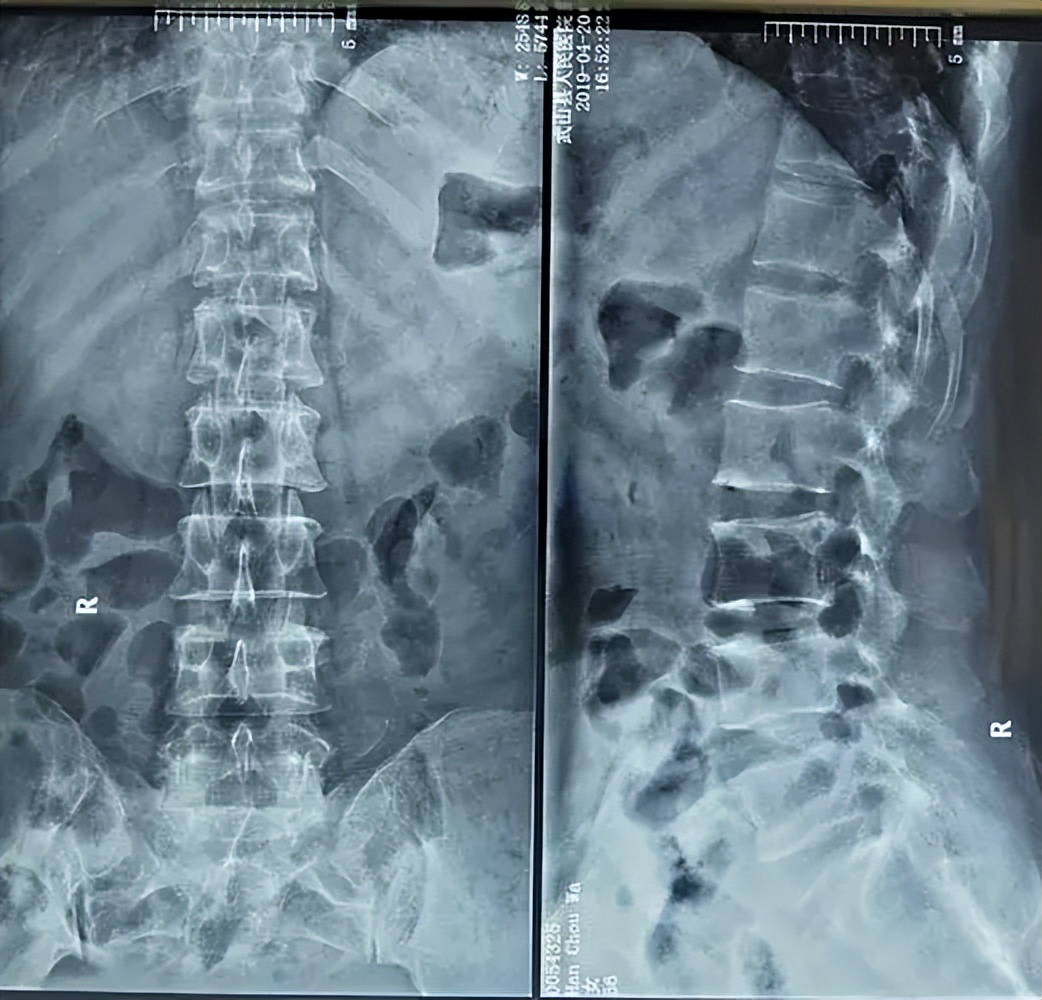

过了一个多小时,张老板回来了,医生看完后告诉张老板:“你看,你这第四腰椎有一些错位,导致四五腰椎间椎间盘突出了,压迫到后面的坐骨神经,所以你这是腰椎盘突出导致的腿麻痛”。